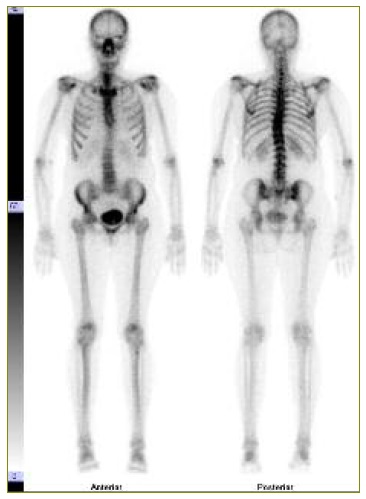

Para avaliação da extensão da doença óssea solicitou-se cintigrafia óssea com 99mTc-HMDP (hidroximetildifosfonato), que demonstrou lesão lítica única na calote craniana, com bordos ligeiramente hipercaptantes, com projeção sobre a sutura lambdoide, localização ligeiramente para-mediana direita. Não se identificaram outras lesões líticas no restante esqueleto (Figura 4).

Figura 4 Cintigrafia óssea com 99mTc-HMDP, varrimento de corpo inteiro, mostrando lesão na calote craniana para-mediana direita. Ausência de outras lesões no restante esqueleto.

O papel da cintigrafia óssea com 99mTc-HMDP, um análogo dos constituintes da matriz óssea, é reservado aos meningiomas durais com calcificação quando apresentam origem ou extensão óssea e para pesquisa de outras lesões no esqueleto.